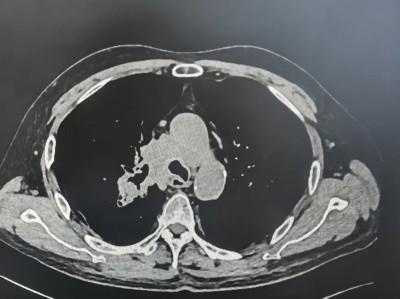

张大叔第三疗程治疗前后对比

治疗第一个疗程后

治疗第三个疗程后

3月下旬,顺利完成第3疗程治疗。复查结果令人振奋:肿瘤显著缩小,侵犯右主支气管的病灶大幅退缩,生活质量明显提升。